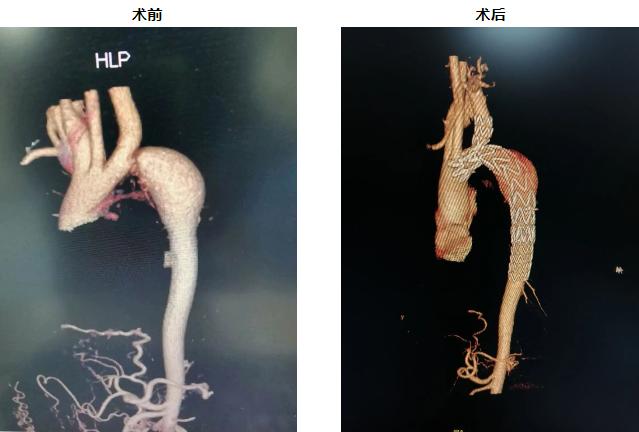

43岁的孟先生有20年高血压病史,长期靠药物控制,效果却一直不佳。最近1个月,他频繁出现胸闷、头晕、头痛的症状,血压飙升至220/111mmHg,在外院治疗无果后转而来到安理大一附院,被门诊以“高血压3级(高危)”紧急收治医院南区。完善检查后发现,患者血管远端可能存在狭窄或梗阻,进一步CTA检查结果更是危险:患者主动脉弓严重狭窄,以至于达到离断等级,血管近乎堵死了!据了解,正常人的主动脉弓应像“桥梁”一样连接升主动脉与降主动脉,为全身重要器官供血。而孟先生的主动脉弓严重狭窄,到了几近闭塞的程度,形成了一个“断桥”,正是这一复杂血管病变,导致他导致上半身血流受阻,引发持续性高血压危象,显著增加了主动脉破裂、脑出血及靶器官损害的风险。

2025年9月28日,经过严密的术前准备,由李晓强院长主刀,手术团队为孟先生实施了“主动脉弓部狭窄球囊扩张、主动脉支架置入、主动脉支架开窗加左锁骨下动脉支架置入”。术中,团队通过右腹股沟和右肘关节两处切口将导丝精准送至升主动脉,造影明确狭窄部位后,逐级球囊扩张、支架覆盖病变段、再次球囊扩张。当支架撑开的瞬间,原本狭窄的主动脉弓血流恢复畅通,侧支血管压力显著下降,造影显示主动脉弓各分支血管血供良好,支架形态稳定。10月14日,团队又为患者实施“腹主动脉导管溶栓术”治疗,术后患者血压控制稳定,状态良好。

本例手术结合了胸主动脉支架置入和左锁骨下动脉重建技术,在血管外科领域属于先进水平,兼备解剖复杂性、技术先进性、风险控制性三大难点,代表了主动脉疾病治疗的高水平技术,通过微创方式解决复杂解剖问题,具有重要的挽救生命和功能保留价值。此次成功救治,标志着安理大一附院在复杂主动脉疾病领域的诊疗水平达到国内一流水准。从多学科联合诊断到个体化精细手术,每一步都体现了团队的专业素养和协作能力,展现了省属三甲医院应对疑难危重病的硬核实力!